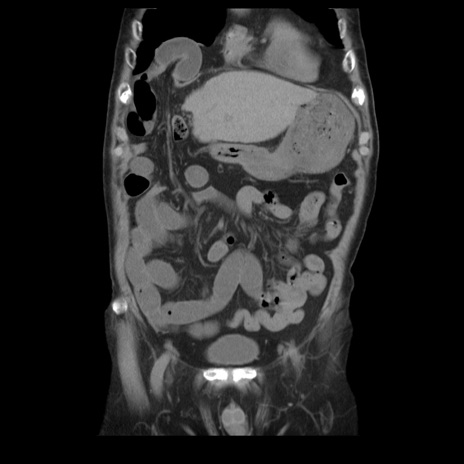

症例21(冠状断像)

【症例】70歳代男性

【主訴】腹痛

【現病歴】肝硬変・肝細胞癌にてかかりつけの方。約9時間前に食後より腹痛出現。症状が徐々に増悪し、嘔吐出現したため来院。

【既往歴】肝硬変、肝細胞癌(RFA、TACE後)